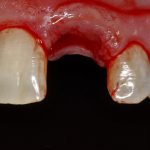

К счастью, уже через 6 недель после операции вдруг выяснилось, что ничего исправлять не нужно:

Фактически, нам осталось лишь дождаться приемлемого уровня остеоинтеграции имплантатов,  — примерно 2-3 месяца, — и можно переходить к постоянному протезированию.

Через три месяца мы сняли коронки с имплантатов, чтобы оценить качество формирования десневого контура:

С этого момента можно перестать переживать — десневой контур сформировался правильно, мы получили достаточный объём и качество окружающей платформу имплантата десны. Можно приступать к изготовлению постоянной протетики. Подрядчиком стала зуботехническая лаборатория French Creative, одна из топовых лабораторий Москвы.